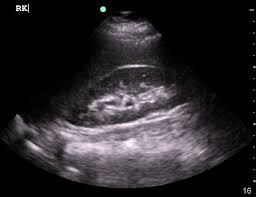

Kidney Ultrasound Emergency Medicine. Found that in the diagnosis of renal calculus the sensitivity of renal ultrasound alone was 93 and specificity 83. A landmark study published in 2014 by the new england journal of medicine conducted at 15 various emergency departments evaluated the accuracy of point of care ultrasound pocus versus computed tomography ct scan as the initial imaging method for patients with suspected kidney stones.

This has been studied formally in both emergency medicine and perinatology and in both cases there were no legal actions related to misdiagnosis. In our 20 years of experience with point of care ultrasound by nephrologists at this institution entailing over 20 000 studies this issue has not arisen once. In the emergency department bedside renal ultrasound has allowed the physician to quickly and accurately assess the kidneys and the bladder for obstruction.

Furthermore patients with a normal renal ultrasound are at low risk for hospitalization or urologic intervention 1 3.